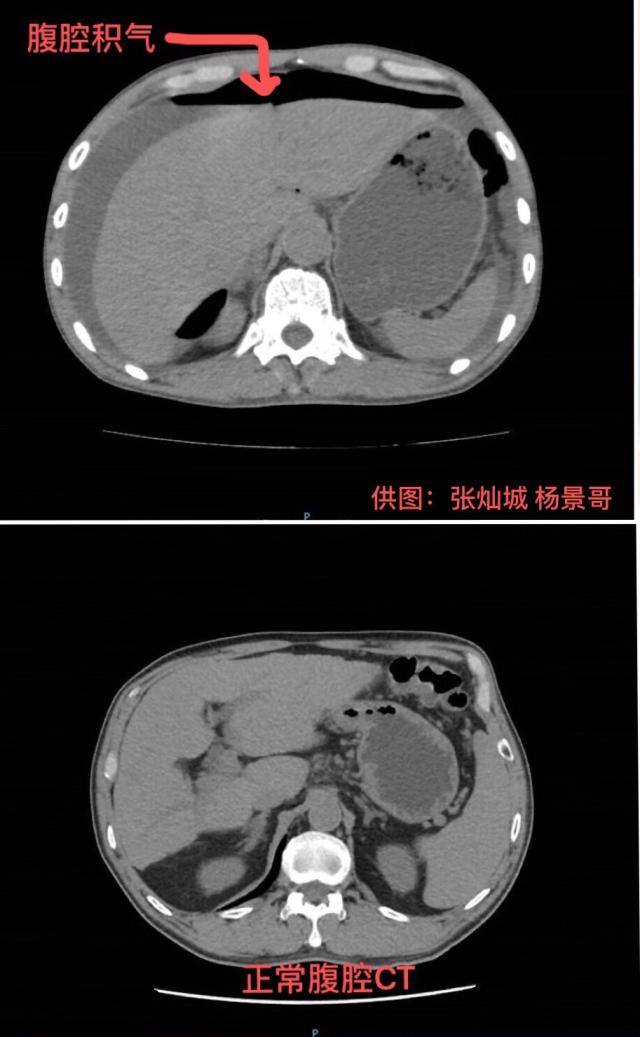

当时,陈伯腹中因大量积水而肿胀发硬,还出现了无尿症状,腹部皮肤因供血不足已出现“花斑”。结合进一步检查结果,诊断为胃穿孔弥漫性腹膜炎感染性休克。“如果不做手术,熬不过当晚。但进行手术,也有极大的风险。”汤汉林说。

暨南大学附属第一医院麻醉科主任医师李雅兰和团队维持着陈伯的生命体征,胃肠外科手术团队迅速进行手术。胃肠外科副主任医师杨景哥介绍,术中从陈伯腹部抽出了2500毫升黄绿色脓液,相当于两支可乐“大炮”,感染十分严重。胃壁上有直径1.5厘米的穿孔,胃液伴随食物残渣就是通过这个洞涌入腹腔。